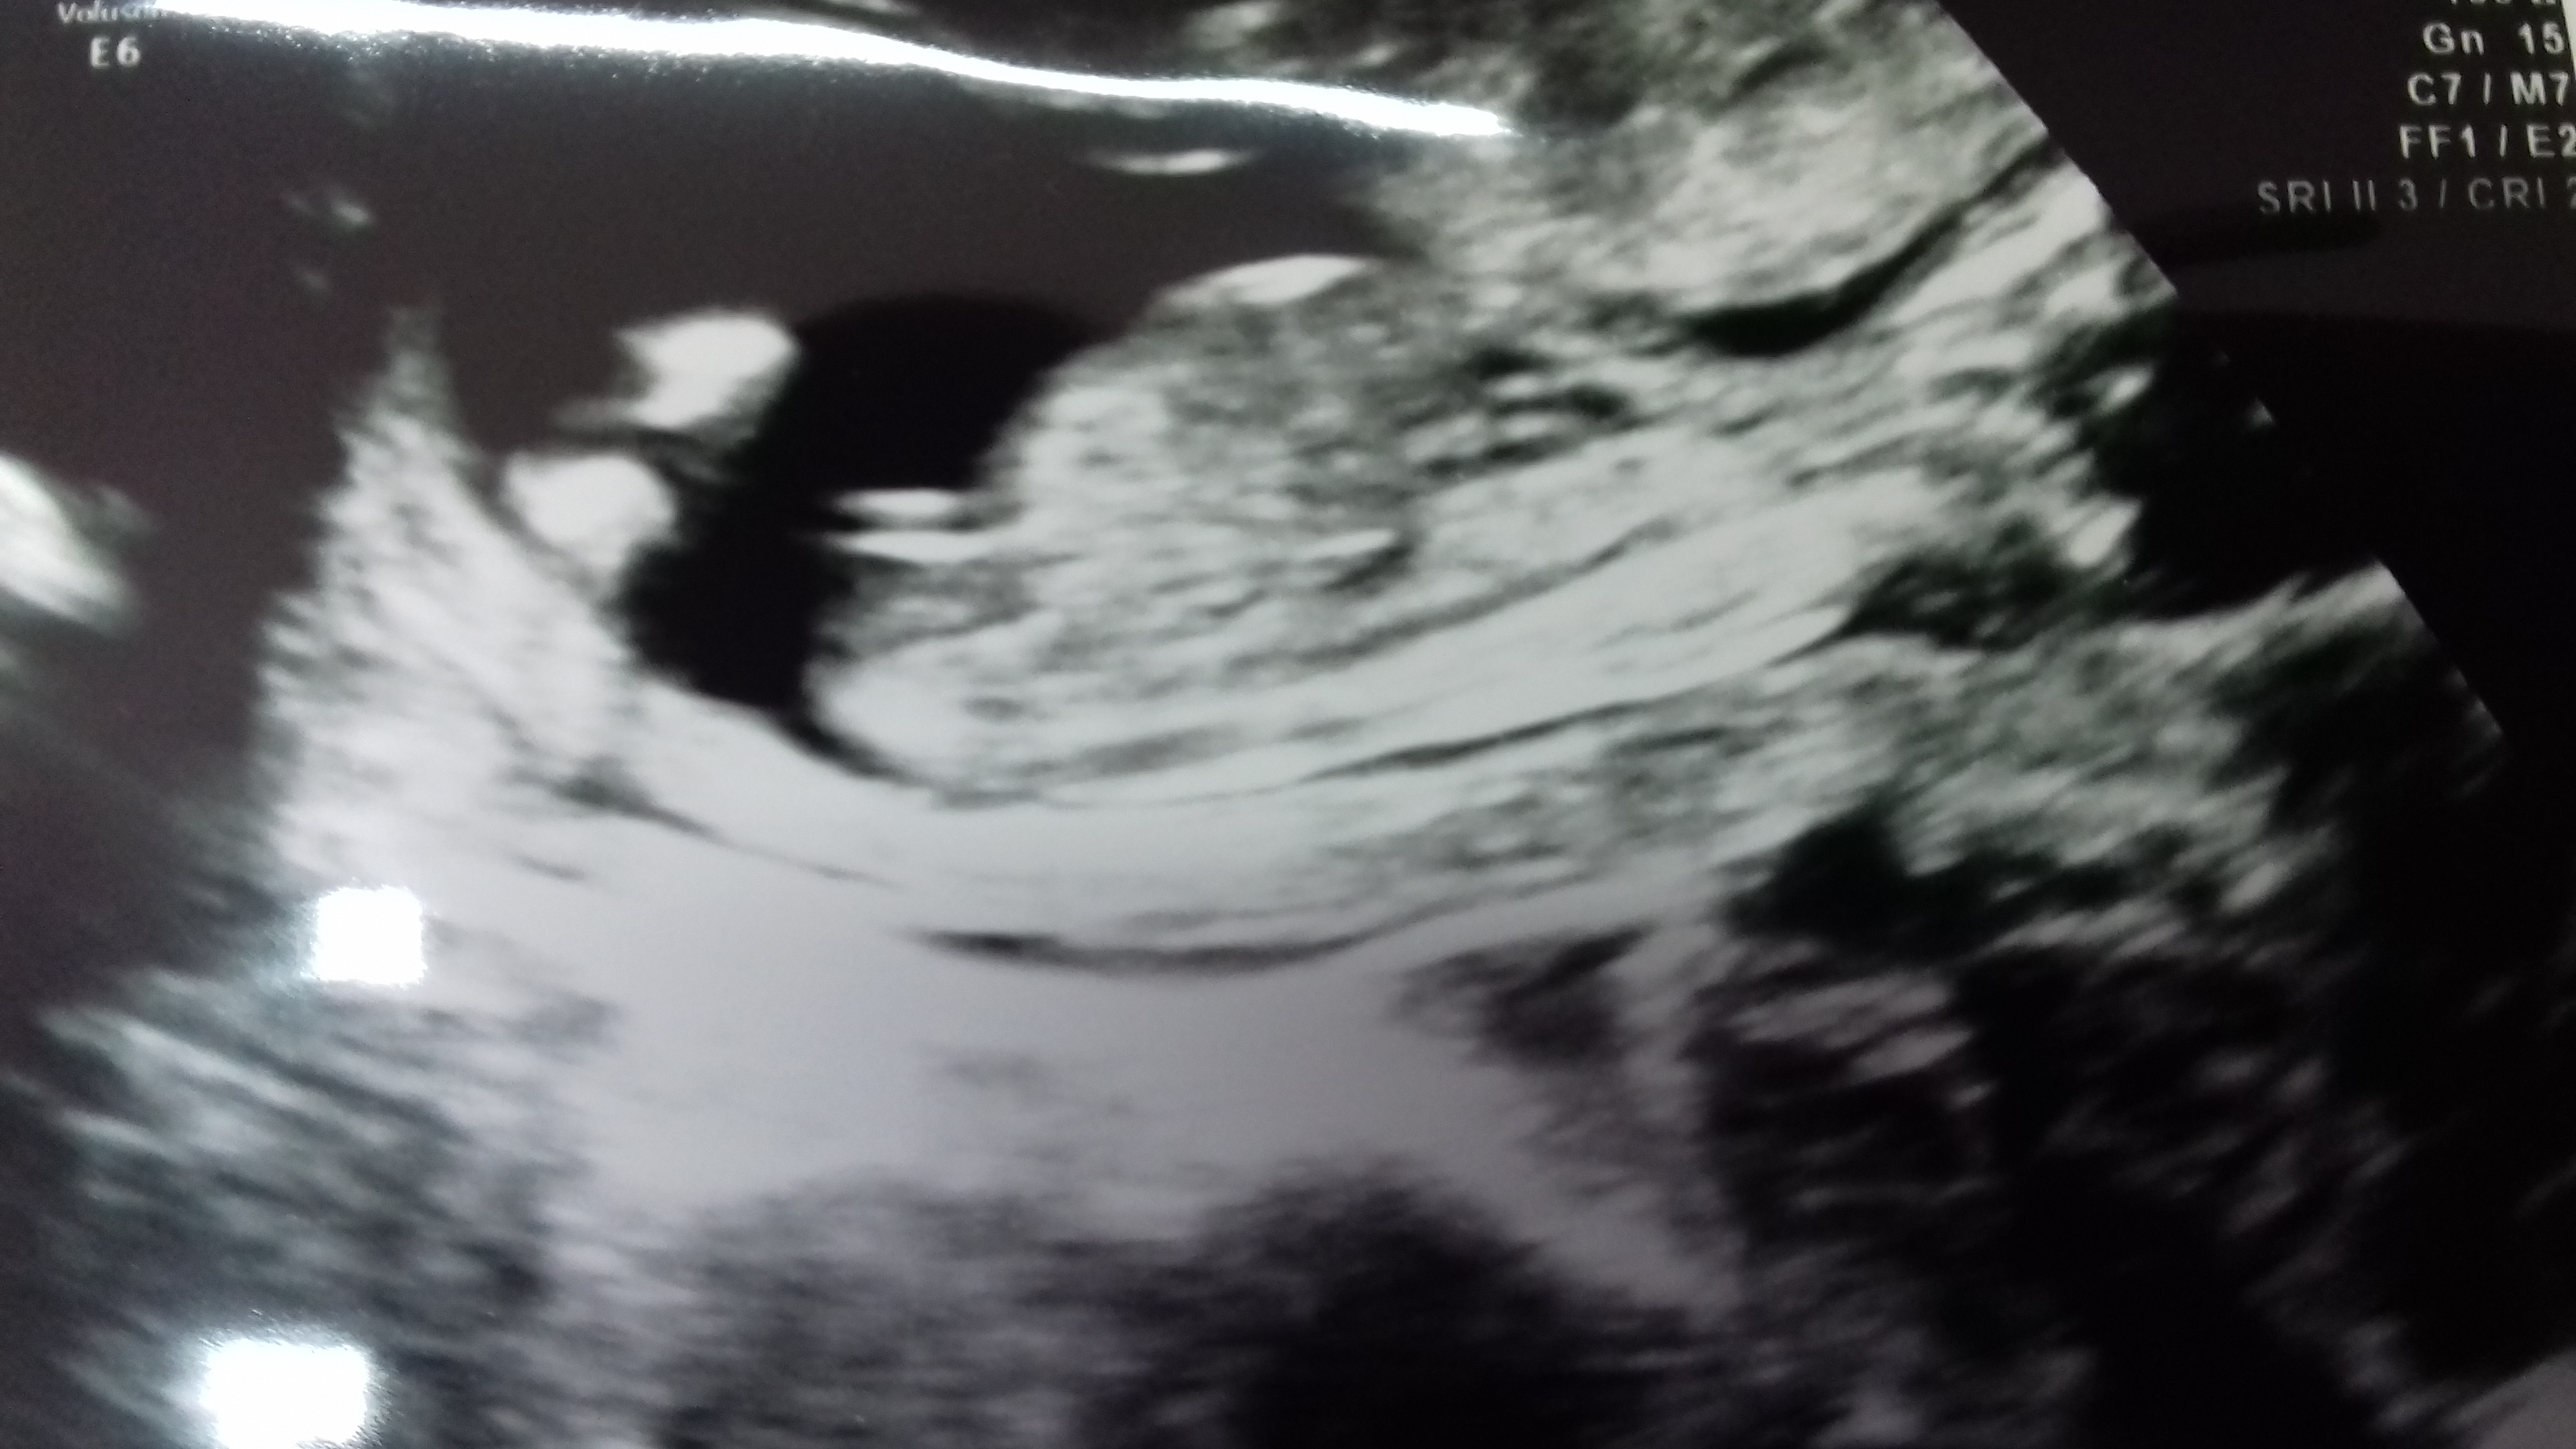

Thoughts please? I already have 3 boys. I wish it is a girl this time but i wont be disappointed either way xx

Girl!

I'm actually leaning boy on this little one. Hope I'm wrong and this is your girl :happy:

This is just a guess, I am no master, but I'm saying boy based on it looks like it 'stacking'. The blob on top of the end of the white line is the new magic tell tale sign, apparently, that means the baby is a boy!

Last pics look more girly but I think boy, hope I'm wrong. First one looks like boy nub and second one would look girly if no stacking (but could very well be baby's leg in the way). Even the last pic has a line under nub which might suggest boy. But really hope it is your baby girl!

I'm leaning girl. What gestation are the most recent pics from? If they are 13+ weeks, then I would most definitely say girl.

It's say on the photo 14 weeks 2 days! X

I'm still leaning more towards girl because at this gestation all of my boys had a clearly visible scrotum and penis. While anything is possible, I think that potty shot is swollen girl bits.